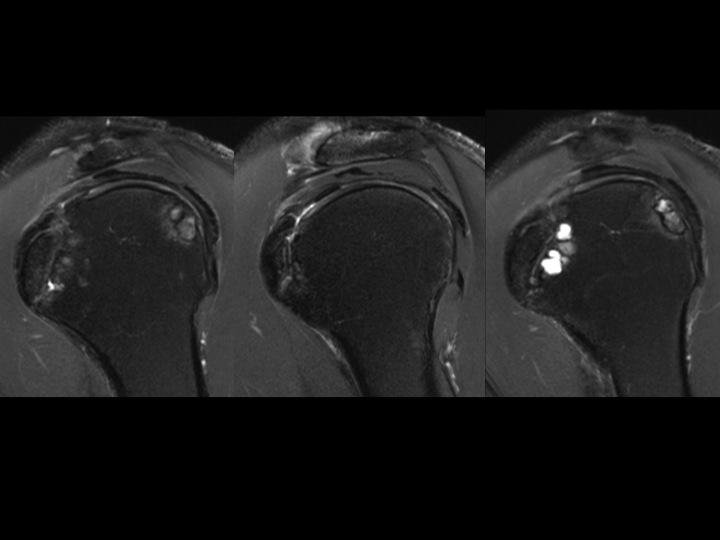

62 yr old male with chronic shoulder pain

It appears that this is more likely to represent an Os Subscapularis than a chronic avulsion fracture non-union of the lesser tuberosity. It seems the ossicle is larger than the normal lesser tuberosity, and the subscapularis tendon appears normal. Cyst-like changes deep to the synchondrosis suggest chronic micromotion. Have any of you seen an Os Subscapularis? Does it exist? I could find no reference. BTW the supra and infra are normal, but there is glenohumeral DJD.

Os Subscapularis vs Old Lesser Tuberosity Avulsion